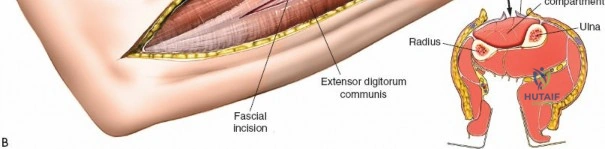

II. Dorsal (Posterior) Approach

The dorsal approach addresses the dorsal and mobile wad compartments.

Incision: A separate straight longitudinal incision is made over the dorsal aspect of the forearm, centered approximately between the ulna and radius, extending from just distal to the lateral epicondyle to the wrist.

This image shows the dorsal longitudinal incision, made directly over the extensor compartment, providing access for decompression. -

Release of Dorsal Compartment: Identify the investing fascia over the extensor muscle group (ECU, EDM, EDC, supinator). This fascia is incised longitudinally throughout the length of the incision. Ensure full decompression of all muscle bellies.

- Proximal Consideration: The supinator tunnel, through which the posterior interosseous nerve (PIN) passes, should be carefully inspected and released if necessary, though it is less commonly a primary compression site in acute compartment syndrome.

The dorsal fascia is incised here, allowing the extensor muscles to expand. The extensor digitorum communis and other dorsal muscles are visible.

- Proximal Consideration: The supinator tunnel, through which the posterior interosseous nerve (PIN) passes, should be carefully inspected and released if necessary, though it is less commonly a primary compression site in acute compartment syndrome.

Release of Mobile Wad (Lateral) Compartment: This compartment contains the brachioradialis, ECRL, and ECRB. The fascia overlying these muscles should also be released through the dorsal incision, often by extending the fascial release more radially. The superficial radial nerve runs deep to the brachioradialis in its distal third; care must be taken to avoid injury during distal extension of the fascial release.

This image illustrates the release of the mobile wad, specifically showing the decompression of the brachioradialis. The full extent of the fascial release should be visualized.